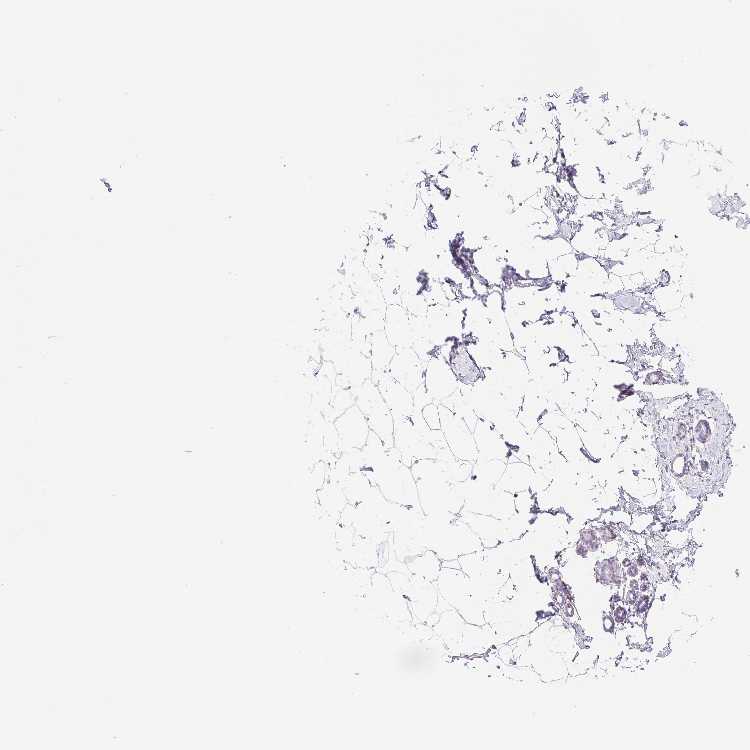

BREAST - Antibody stainingi

Antibody staining in the annotated cell types in the current human tissue is reported as not detected, low, medium, or high, based on conventional immunohistochemistry profiling in selected tissues. This score is based on the combination of the staining intensity and fraction of stained cells.

Each image is clickable and will lead to virtual microscopy that enables deeper exploration of all samples and also displays staining intensity scores, fraction scores and subcellular localization as well as patient and tissue information for each sample.

Antibody HPA062430Antibody HPA062494

Adipocytes Not detectedNot detected

Glandular cells Not detectedNot detected

Myoepithelial cells Not detectedNot detected